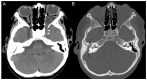

Results: A 6-year-old patient was admitted for right otomastoiditis and thrombosis of the sigmoid and transverse sinuses, as well as the proximal portion of the internal jugular vein. Radiological examinations revealed a left orbital mass (22 × 14 mm) compatible with asymptomatic orbital meningocele (MC) herniated from the superior orbital fissure (SOF). The child underwent a right mastoidectomy. After the development of symptoms and signs of intracranial hypertension (ICH), endovascular thrombectomy and transverse sinus stenting were performed, with improvement of the clinical conditions and reduction of the orbital MC. The systematic literature review encompassed 29 publications on 43 patients with spontaneous orbital MC. In the majority of cases, surgery was the preferred treatment.